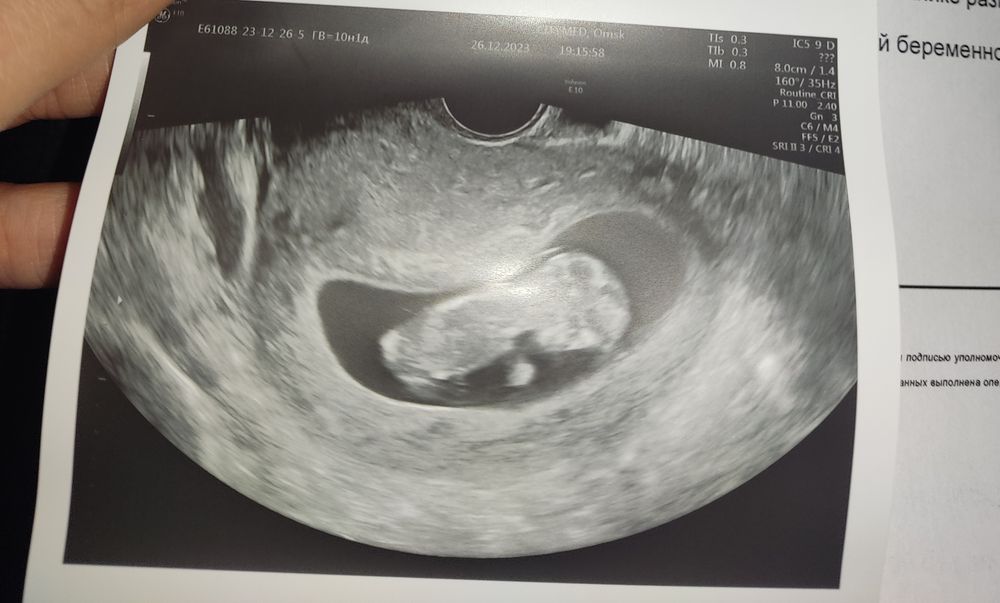

Девочки, по УЗИ опережаем